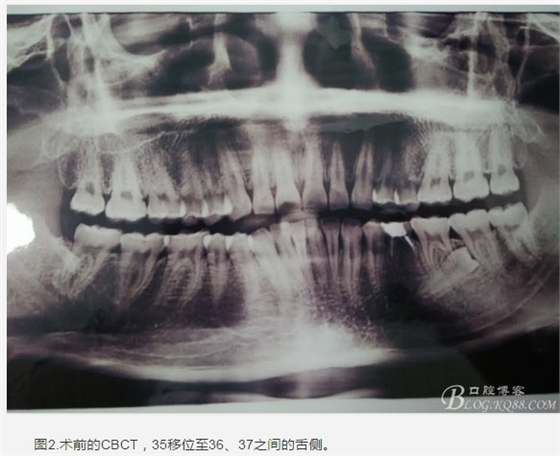

患者、盧xx、男、19歲。主訴:左側(cè)下頜乳磨牙未脫落,要求檢查。??茩z查:左側(cè)下頜第二乳磨牙有充填物。無松動(dòng),全景片檢查。35移位至36、37之間。頰舌側(cè)均不能觸及隆起。CBCT檢查:35位于36、37的舌側(cè)。表面骨質(zhì)約2mm左右。35完全骨埋伏,36的遠(yuǎn)中牙根疑是吸收。建議35暫觀察。置留不取。患者要求拔除擔(dān)心壓迫36牙根或者發(fā)生囊性變。術(shù)前簽手術(shù)同意書。

圖1.術(shù)前的全景片影像檢查,35移位至36、37之間。